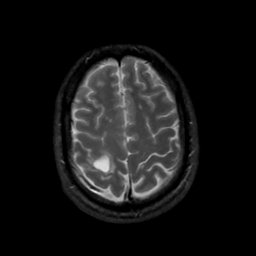

MR Study #8, March 31, 1991 -- Slice #40